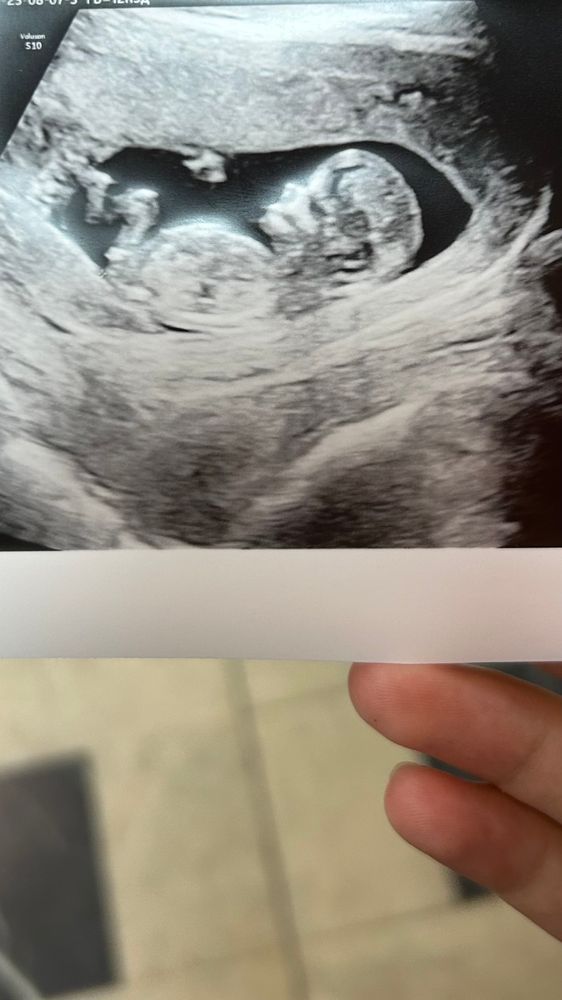

Пол малышаЗдравствуйте, девочки, тут есть опытные мамочки которые смогут по фото понять мальчик или девочка?😀

вчера делали скрининг сказали, что с большим сомнением - может быть девочка, я не знаю почему большие сомнения, я вроде вижу девочку)))

Ну если то, что видно - это половой бугорок, то девочка. Но не факт)

А мне кажется, что форма головы прям пацанячья) но я тот ещё эксперт, конечно 😁